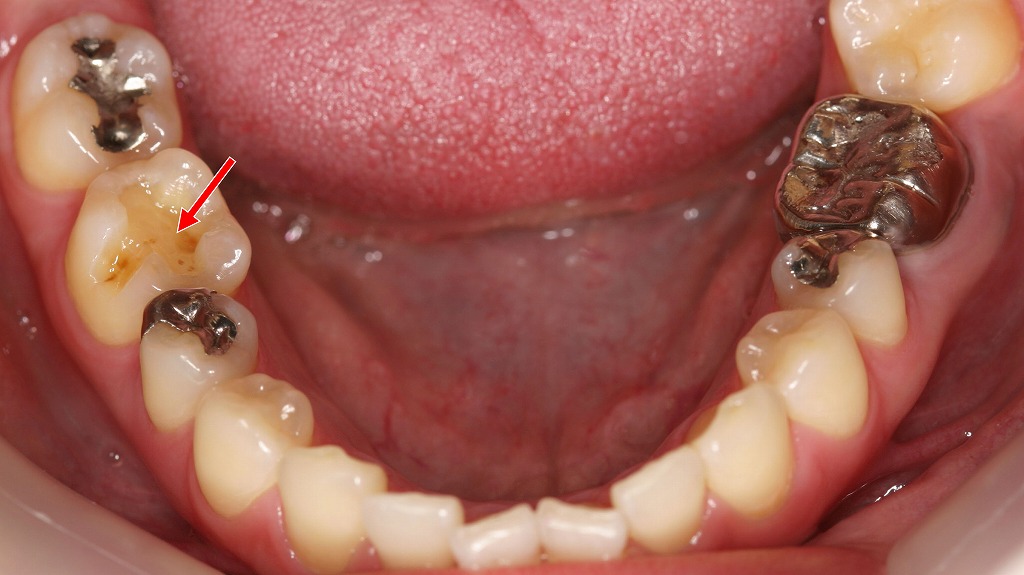

この画像は上顎(口蓋側)から撮影された口腔内写真です。赤い矢印で示されているのは「右上第1小臼歯(4番)」の部位です。

🦷 状況の説明

- 右上4番のメタルインレー(銀の詰め物)が脱離しています。

本来は咬合面(噛む面)に金属の詰め物があったと考えられますが、それが外れてしまっています。 - 内部にう蝕(虫歯)が進行しています。

詰め物が外れた後、放置されたことで細菌が入り込み、象牙質の部分が茶色く軟化しているのが確認できます。 - 隣の歯(右上5番)が4番方向へわずかに移動しています。

長期間詰め物が外れたままにしておくと、歯が空隙を埋めようと移動し、接触関係(コンタクトポイント)が変化します。

その結果、清掃がしづらくなり、さらに虫歯や歯周病のリスクが高まります。

🔍 他の歯の状態

- 前歯部(1〜3番)には歯石や着色沈着が見られます。

定期的なスケーリング(歯石除去)が必要な状態です。 - 左右の奥歯には**金属修復(インレー)**が複数あり、過去に治療歴があることが分かります。